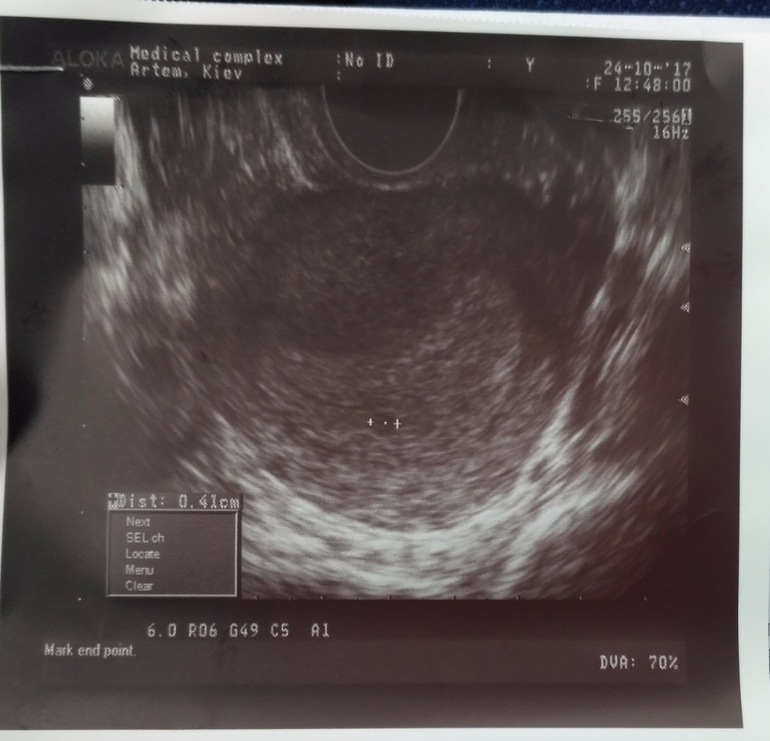

Результаты УЗИ:

УЗИст сказала есть непонятное "включение" в матке очень похожее на малыша, но на таком сроке задержки должно быть не 4 мм как у меня, а около 8-10 мм, и она б его увидела при узи по животу, а это рассмотрели только в матке. Сказала что скорее всего или это не беременность, или я позже забеременнела и у меня срок меньше, потому такое маленькое. Если в течение этой недели не начнется менструация, то через неделю опять к ней на осмотр.